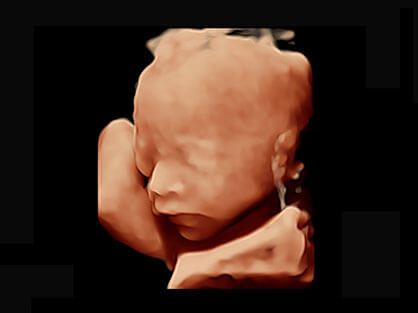

作为P系列家族成员之一,P40 Plus采用九州酷游高端超声系统平台——极光,并以时尚秀丽、小巧灵动的外观设计绽放出灵动之韵、科技之美。高端平台的使用保证了P40 Plus优质的基础图像;完备的高级功能可满足您全身应用的基本需求;丰富的探头配置、多样的高级4D成像及分析软件为您日益增多的妇产应用需求提供丰富的诊疗方案。

可同时显示组织结构表面和内部的轮廓信息,达到透视效果,为临床提供更丰富的诊断信息。